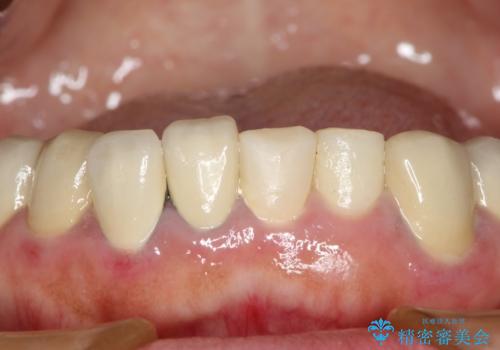

- 下顎の前歯に激痛を覚えて来院された患者様です。

取り急ぎ下顎前歯数歯の根管治療を、銀座しらゆり歯科医院長の林先生にお願いし、それ以外に気になっている、不自然な色調のクラウン、金属部分が見えてブラッシングがしにくいインプラント補綴、口元の突出感、出血のしやすい歯周ポケットなど、全てを解決するための治療を行うこととしました。

期間と費用はかかりましたが、気になっていた部分全てを改善でき、患者様には大変満足していただきました。